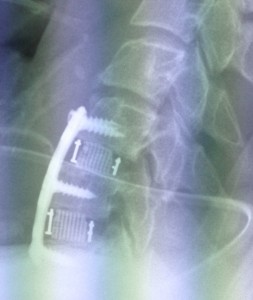

At operation the C6/7 was grossly disrupted and gaped open whilst the C5/6 was less affected. A two level discectomy and fusion was undertaken (see right image) and fortunately the patient was able to be discharged without any persisting neurology 4 days later.